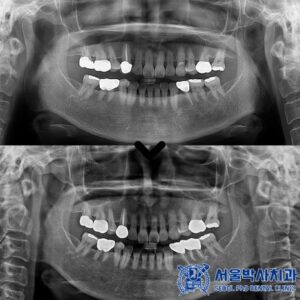

신흥동치과 어금니가 없어서 불편해요 (임플란트와 레진, 크라운 치료 사례)

신흥동치과 어금니가 없어서 불편해요 (임플란트와 레진, 크라운 치료 사례) 안녕하세요. 신흥동치과 서울박사치과입니다. 치아가 상실된 상태로 지내다 보면 반대편 치아가 내려오거나, 주변 치아가 빈 공간으로 이동하면서 전체적인 교합(물리는 힘의 균형)이 흐트러질…